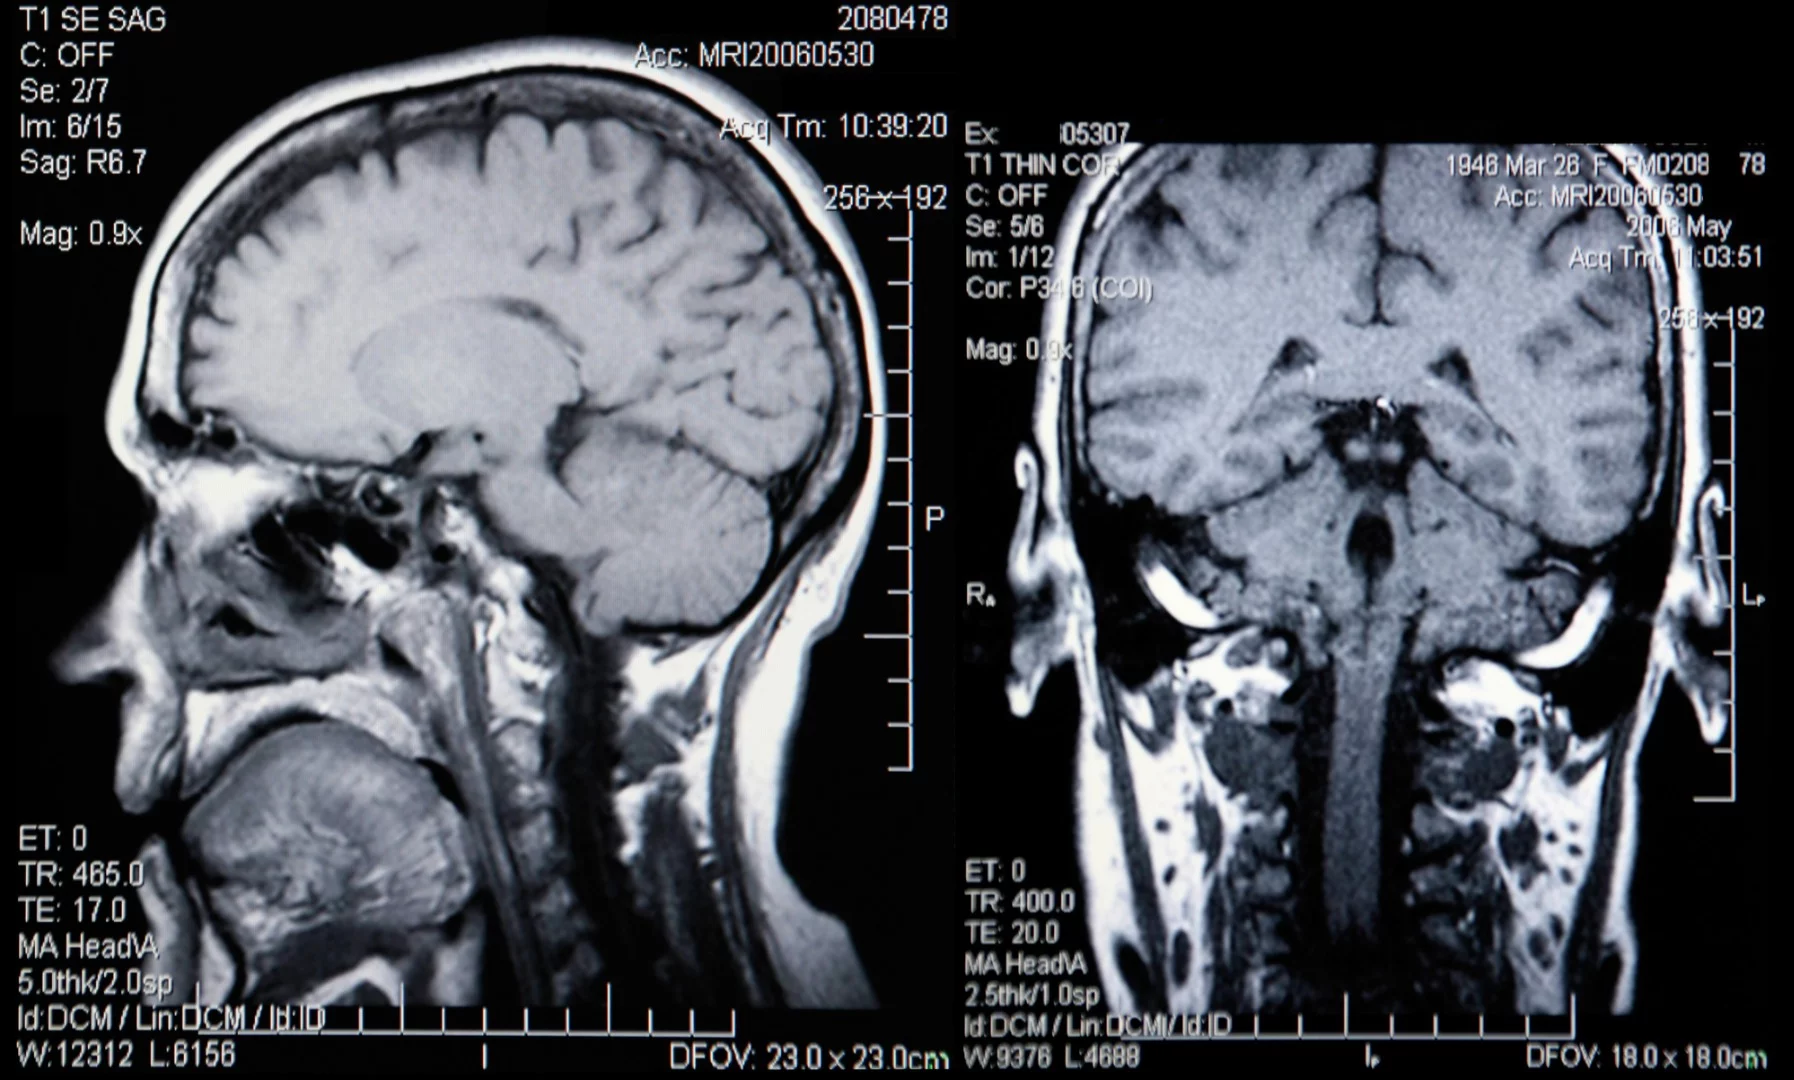

While your chronological age will tell you how long you've been riding around on this planet, your biological age might actually be a more important number, as it tells you how well your body is faring on its journey. Now, researchers at Imperial College London have added to the growing toolbox of biological age determinants by examining images of our brains.

About two years ago, researchers developed a test that could determine your biological age by searching for 150 active genes in the blood. That's also about the time that researchers came up with a different way of determining biological age by examining urine samples. Now, the IC London researchers believe they have found yet another way to determine how well we're aging by combining MRI scans of the brain with machine-learning algorithms. If their method is perfected and verified, finding out our biological age might be as simple as getting a picture snapped of our noggins.

The technique at the heart of the new method was actually initially developed in 2010 and involves using machine learning to analyze measurements of brain volume to estimate the total loss of grey and white matter, a process that naturally occurs as we age.

The twist on the process, which has been described today in the journal Molecular Psychiatry, involves comparing the reduction in brain volume seen in MRIs to a standard developed by examining the brains of 2,000 healthy people. In other words, the 2,000 healthy MRIs were used to create a map that shows what a healthy brain should look like. By comparing new scans to this data, researchers are able to see how much brain matter has been degraded and come up with a biological age for the patient.